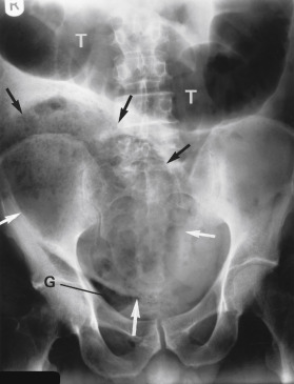

What does this x-ray show?